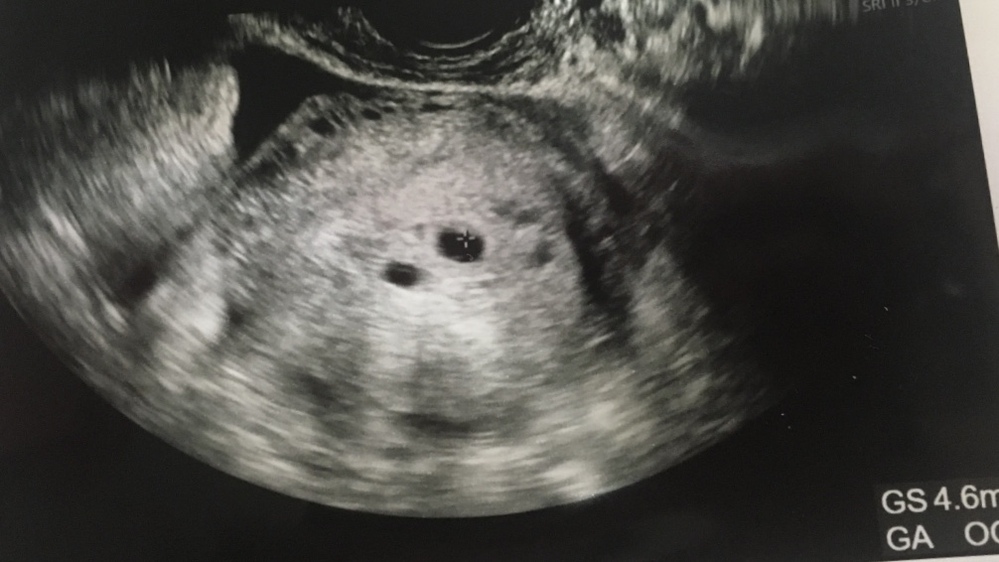

これって双子ですか 妊娠6週目のエコー写真です初めての妊娠で分か 妊娠 教えて Goo

妊娠6週のエコーです 白い影が2つ見えるのですが双子ですか 先生には何 Yahoo 知恵袋

妊娠6週から7週だと言われたのですが これは双子ではないですよね 双子のよう Yahoo 知恵袋